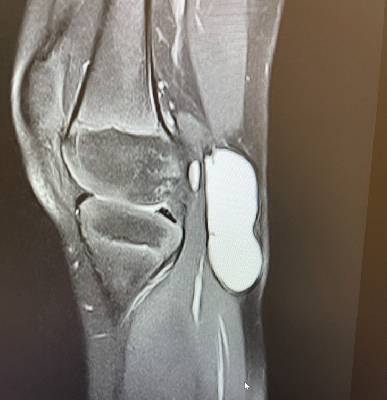

I went for wrist pain and Dr. Haytham Elkhatib Orthopedic treated me with utmost care and

professionalism. Even taking extra time to explain to me the diagnosis in simple terms .

Thank you so much Dr. Haytham ·